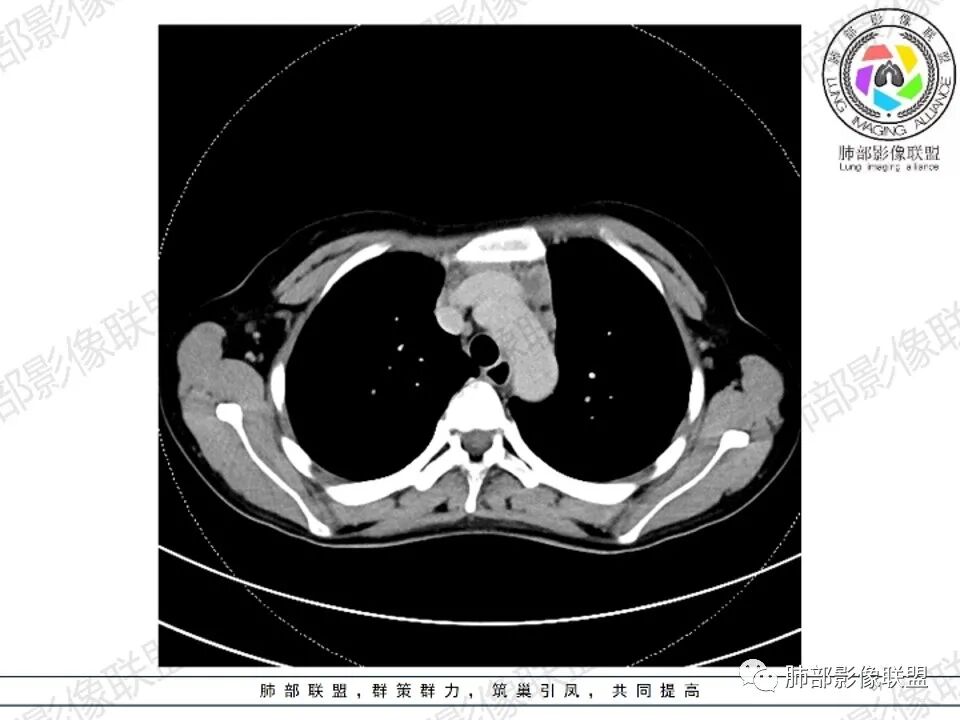

女,27,间断头晕、乏力3年,左眼视物模糊2月。贫血。胸部CT:前纵隔不规则肿块,多结节融合,边界不清,沿主动脉及肺动脉间隙生长,平扫密度欠均匀,增强扫描可见多发低密度坏死,纵隔血管供血穿行,腋窝多发大小不等淋巴结肿大。考虑恶性病变,胸腺癌?肉瘤?淋巴瘤?鉴别胸腺瘤、结节病等。

前纵隔和双侧腋窝多发的淋巴结肿大,前纵隔为甚,融合呈中等强化,部分坏死呈低密度,包埋肺动脉主干和左心缘,融合斑块状,内见血管飘浮特点,前纵隔脂肪间隙混浊,首选淋巴瘤!

CT:定位纵膈病变,前中纵隔多发肿块,质软,塑形,密度不均匀,边界清楚。增强不均匀强化,坏死边界清楚,血管漂浮征。双侧腋下多组淋巴结肿大,明显异常强化。

2.影像显示前纵隔不规则块状影,依势贴附心脏大血管旁,密度不均,边界不甚清楚,有结节融合感。

3.病灶轻度不均匀强化,可见血管穿行,散在液性低密度区。

双肺门未见肿大淋巴结。

4.双侧腋窝区见增大淋巴结,边界清楚。

1.年轻女性,前纵隔不规则块状影,密度不均,边界不甚清楚,有结节融合感,轻度不均匀强化,可见血管穿行,最常见最符合的无疑是淋巴瘤!